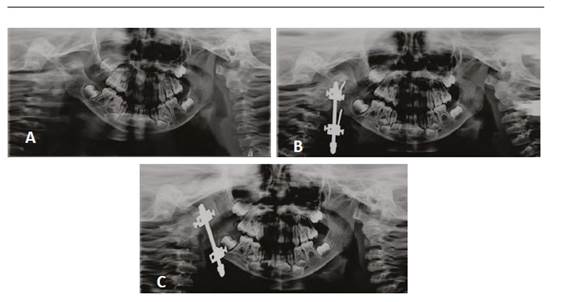

La distracción ósea se basa en el principio de tensión-estrés para permitir el alargamiento óseo y de tejidos blandos a partir de la separación controlada de segmentos óseos (Figura 3). Para ello existen diversos tipos de distractores, los cuales se pueden categorizar en dos áreas. De acuerdo a su ubicación, los distractores pueden ser extraorales e intraorales; mientras que, según la cantidad de vectores con los cuales trabajan, éstos pueden ser univectorial o unidireccional, o bidireccional (plano horizontal y vertical) o multidireccional (plano horizontal, vertical y transversal).51

En las imágenes se observan las ortopantomografías de una paciente de 3 años de edad con MHF tipo II durante la distracción ósea con aparato extraoral. La imagen A corresponde a la radiografía inicial. La imagen B corresponde a la radiografía de control una vez instalado el distractor. La imagen C se tomó luego de un mes de distracción. Nótese el cambio de inclinación del distractor, el aumento en la simetría mandibular y la mejor relación de las piezas dentarias.